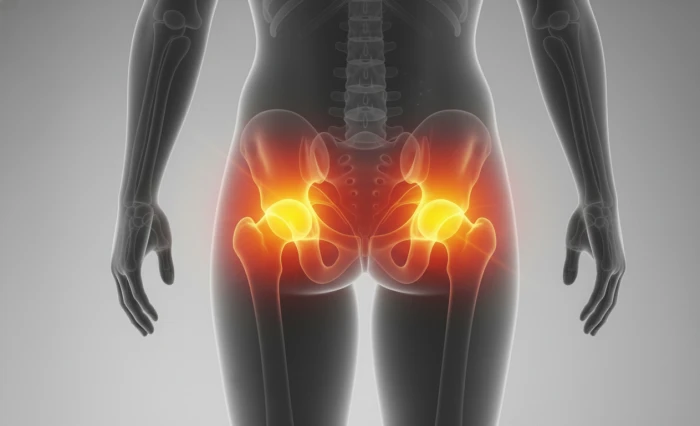

Procedimento indicado para artrose avançada, proporcionando alívio da dor e recuperação da mobilidade.

Conflito mecânico na articulação, causa comum de dor no quadril em pacientes jovens.

Condição degenerativa que causa dor e limitação de movimento na articulação do quadril.

Inflamação na lateral do quadril que causa dor localizada, tratável com fisioterapia.

Dor localizada nas nádegas, que pode irradiar para as pernas, causada por sobrecarga muscular ou compressão nervosa.